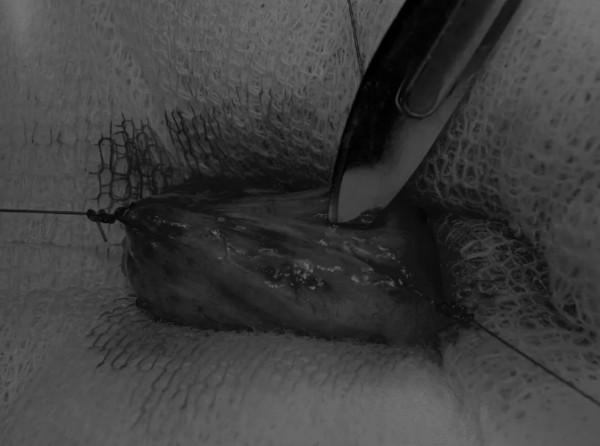

在牵引缝线之间选择血管扩张较差的区域用手术刀切开膀胱壁(图3)。在牵引缝合线之间用手术刀在血管不良的区域做切口。切开膀胱壁后,膀胱内的手术可按手术方案实施,例如取出结石(图4)。

图3 避开主要的膀胱血管,做一个尽可能小的切口

切口可以在膀胱背侧或腹侧进行,避免对大血管的损伤。